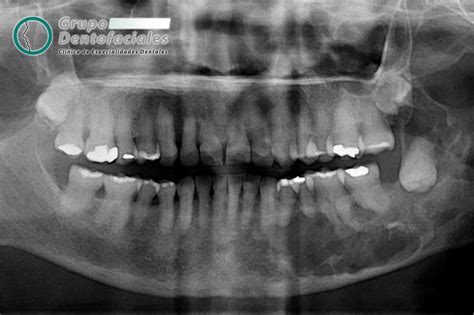

Para determinar el impacto potencial de las muelas del juicio, los ortodoncistas utilizan diversas herramientas diagnósticas, como radiografías y evaluaciones clínicas. Estas evaluaciones permiten a los profesionales anticipar problemas y planificar adecuadamente el tratamiento.

Las radiografías revelan la posición y el desarrollo de las muelas del juicio, permitiendo identificar si estas se encuentran impactadas, es decir, si no tienen espacio para erupcionar correctamente. Adicionalmente, el ortodoncista analiza la mordida del paciente y el espacio disponible en la boca para determinar si las muelas del juicio podrían generar apiñamiento, desplazamiento o daño en los dientes adyacentes.

- Radiografías: Muestran la posición y desarrollo de las muelas del juicio.